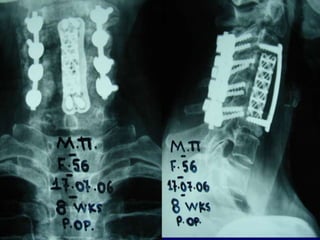

2nd case

Ma. Pal.

F 56 – Lawyer

Symptoms

 Neurologic deficit

 Cervical Pain

 Low fever

Laboratory

 Neutroph. ↑

 SR 50

56

X-rays

Anterior procedure

Vertebrectomy - PUS evacuation + Stabilization

Posterior stabilization

2nd Post op.

MRI

Follow up

Pus culture

(staphylococous aureous)

Antibiotics

 i-v for 2 mts

 orally for 6 mts

Complete neurologic recovery